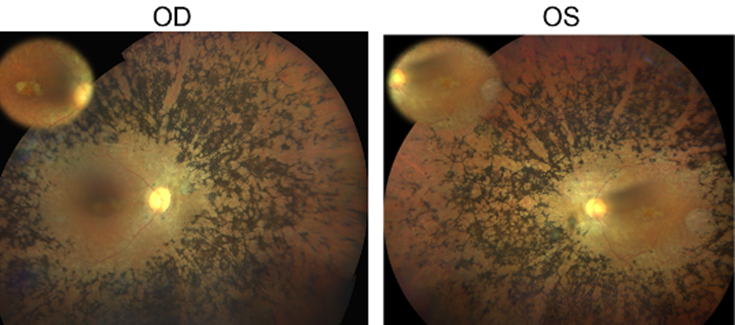

(*) Explicación de la figura: Fondo de ojo del paciente con retinitis pigmentosa en el que se ha identificado la mutación en el gen CFAP20. OD=ojo derecho, OS=ojo izquierdo.

Por último, la estrategia validada se ha aplicado sobre un conjunto de 14 individuos pertenecientes a familias de DHR sin causa genética conocida. Como resultado de ello se ha podido identificar una variante en el nuevo gen candidato CFAP20 (c.337C>T; p.Arg113Trp) que segrega con la enfermedad en una familia consanguínea de RP no sindrómica.